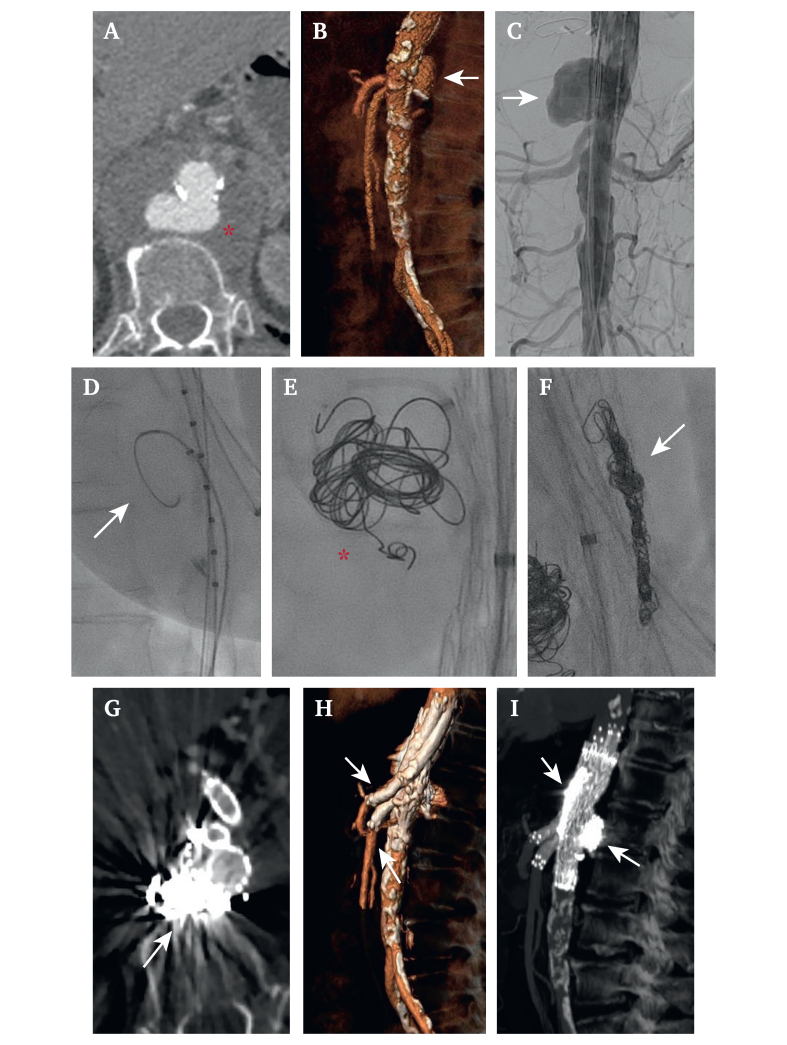

Paravisceral aortic lesions present significant challenges for endovascular treatment. This retrospective analysis of consecutively treated patients from April 2017 to June 2021 aimed to analyse the outcome of primary intra-operative embolisation of aortic complicated pseudoaneurysms and gutter channels during parallel graft (PG) repair of paravisceral symptomatic aortic pseudoaneurysms.

Patients with symptomatic pseudoaneurysms of the paravisceral aorta treated with PGs using chimney or periscope configurations were included. Thoracic endografts were positioned to exclude the aortic lesions. Coil embolisation of both the lesions and gutter channels was performed after graft deployment and prior to ballooning of the stent grafts. The primary endpoints were technical success (defined as exclusion of the pseudoaneurysm, target visceral vessel [TVV] patency, absence of gutter endoleaks) and clinical success (technical success + resolution of symptoms + absence of major adverse events) at 30 days. Secondary endpoints included overall survival, TVV patency, gutter endoleaks, and freedom from re-interventions during follow up.

Six patients (four women) were treated for pseudoaneurysm rupture (three cases) and symptomatic aortic pseudoaneurysm (three cases) of the paravisceral aorta. The patients' anatomies were unsuitable for off the shelf devices and patients were all deemed to be at prohibitive surgical risk. A total of 15 TVVs were revascularised (comprising three coeliac arteries, five superior mesenteric arteries, and seven renal arteries) using 10 chimney and five periscope PGs. One coeliac artery was occluded. Seventy coils were deployed to embolise both the aortic ruptures and gutter channels. Both technical and clinical success rates were 100%. The median follow up was 17 months (IQR 5, 35), during which time three patients died due to non-aortic related causes. One coeliac artery (6%) was occluded, and no endoleak evidence was found.

Primary intra-operative embolisation during parallel graft endovascular repair of paravisceral symptomatic aortic pseudoaneurysms may be both safe and effective in excluding the pseudoaneurysm when other options are unavailable.